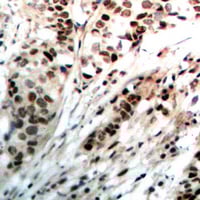

IHC (Immunohiostchemistry)

(Immunohistochemical analysis of Progesterone Receptor staining in human breast cancer formalin fixed paraffin embedded tissue section. The section was pre-treated using heat mediated antigen retrieval with sodium citrate buffer (pH 6.0). The section was then incubated with the antibody at room temperature and detected using an HRP conjugated compact polymer system. DAB was used as the chromogen. The section was then counterstained with haematoxylin and mounted with DPX.)